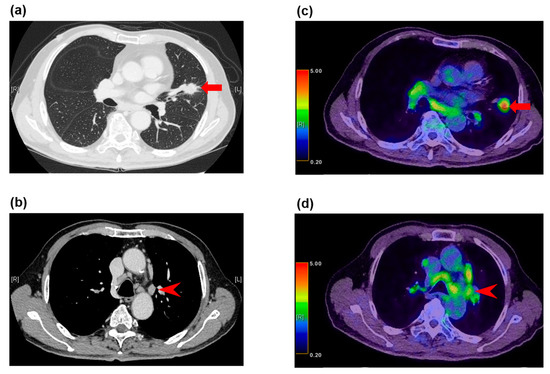

Figure 1.

False negative fluorodeoxyglucose F 18 positron emission tomography (FDG-PET) findings in normal-sized lymph nodes in a 79-year-old woman with adenocarcinoma. (a) The computed tomography (CT) image shows a left upper lobe tumor (arrow), (b) and nonenlarged station 5 lymph nodes (arrowhead). (c) The FDG-PET/CT image shows FDG accumulation with a maximum standardized uptake value (SUV) of 3.3 (arrow) in the adenocarcinoma in the left upper lobe, (d) and no FDG accumulation in the normal-sized station 5 lymph nodes (arrowhead). These lymph nodes demonstrated metastatic disease at histopathologic examination of the specimen from surgical biopsy.